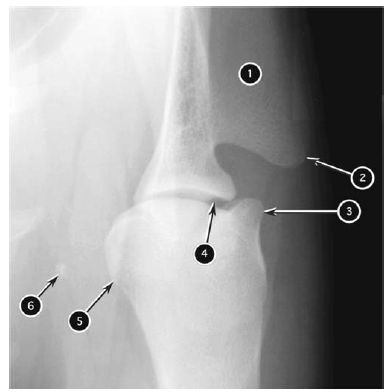

Craniocaudal radiograph of canine elbow joint

What number?

- Supratrochlear foramen of humerus

- Medial epicondyle of humerus

- Lateral epicondyle of humerus

- Trochlea of humeral condyle

- Capitulum of humeral condyle

- Anconeal process of ulna

- Tuber olecrani of ulna

- Medial coronoid process of ulna

- Head of radius

A

1. Tuber olecrani of ulna

2. Medial epicondyle of humerus

3. Trochlea of humeral condyle

4. Medial coronoid process of ulna

5. Head of radius

6. Capitulum of humeral condyle

7. Lateral epicondyle of humerus

8. Anconeal process of ulna

9. Supratrochlear foramen of humerus